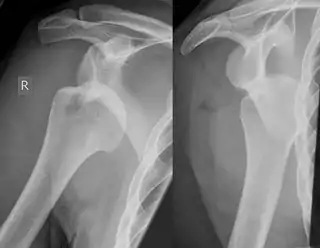

Lesión de Hill Sachs

Una lesión de Hill Sachs, también llamada fractura de Hill Sachs, es una depresión cortical en la parte posterolateral de la cabeza humeral.[1] Sucede a causa de la impactación de la cabeza humeral contra el reborde glenoideo anteroinferior al producirse una dislocación anterior del hombro.

![]() Luxación de hombro derecho con lesión de Hill Sachs | ||

La lesión de Hill Sachs puede encontrarse hasta en el 92 % de las dislocaciones anteriores recurrentes. La prevalencia general en las dislocaciones es del 35-76 %.[4] Su presencia, por lo tanto, puede ser utilizada como marcador de que ha existido una dislocación aun cuando el húmero haya vuelto a su posición original.

La mayor parte de estas fracturas se encuentran a través de estudios radiológicos convencionales. Una radiografía posteroanterior con el brazo en rotación interna ofrece una buena visión del defecto, mientras que visiones axilares con el brazo en rotación externa tienden a ocultarlo. La sensibilidad y especificidad de la radiografía se encuentra en un 65 % y 67 %, respectivamente. La ultrasonografía también ha demostrado ser un método útil para identificar esta lesión, con una sensibilidad del 96 % y una especificidad del 100 %.